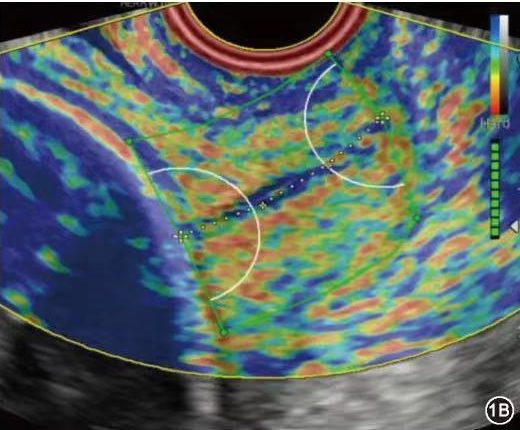

宫颈弹性成像技术是利用生物内部作用力如子宫动脉搏动及呼吸触发宫颈组织应变而获得宫颈各弹性参数,间接评估宫颈硬度,不受操作者影响。该技术是一种相对简便、直观、可重复操作的早产监测手段。应用二维灰阶超声联合E-cervix超声弹性成像,可为评估高危孕妇妊娠宫颈成熟度变化提供参考,对临床早期干预具有一定辅助价值。

临床上对于无症状高危孕妇一般通过经阴道指检判断宫颈软硬度对孕妇的早产概率进行预测,但该诊断方法尚无统一判定标准,仅凭检查者的主观意识进行诊断,极易影响检查结果。超声宫颈长度被认为是评估早产常用且有效的测量指标,尽管宫颈长度测量已成为临床实践的常见检查,仍有多数宫颈短小且无sPTB病史的孕妇在没有干预的情况下足月分娩,以及较多宫颈长度正常的孕妇发生早产。因为孕期宫颈胶原变化会先于宫颈缩短,而这些变化会让宫颈变软、托举力下降,传统方式(宫颈触诊、宫颈长度测量)难以捕捉。宫颈弹性成像技术有助于更早发现这种改变,并提供宫颈软硬程度的量化参考信息。